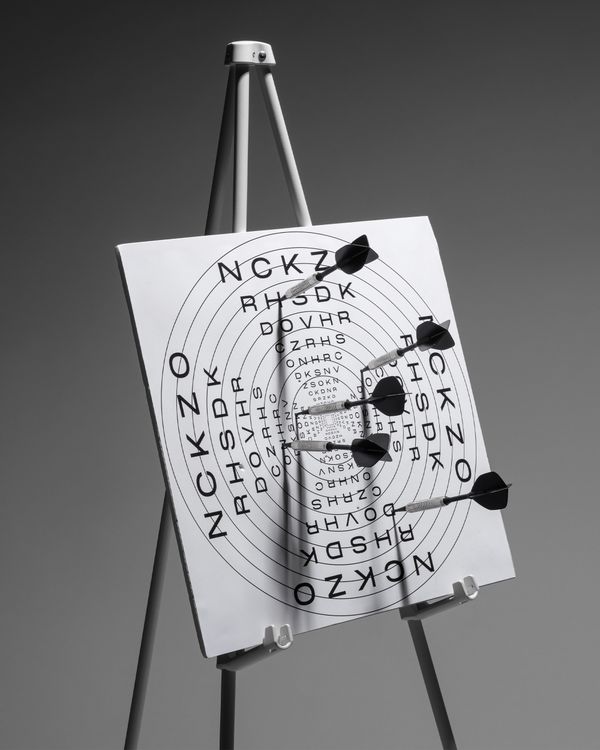

By comparing Eastern and Western myopia prevention, the project reveals how both transform health practices into systems of discipline, showing that “tradition” and “science” alike serve as tools of social and medical control.

China's standardized eye exercises combine traditional massage with mechanized discipline norms. As a state-mandated body ritual, it shapes explicit disciplinary instructions through unified acupoint stimulation and rhythmic music. This practice not only inherits the theory of traditional Chinese medicine, but also implies the contradiction of efficiency management in the industrial era. In contrast, the West uses technical means such as orthokeratology lenses and visual training to conduct individualized interventions, enforce self-monitoring through precise procedural norms, and embed invisible discipline into medicalized self-care.

Despite cultural differences, both systems enforce standardized body behaviors through unique but overlapping disciplinary logics, making them no longer just neutral health practices, but invisible mechanisms of social control. By juxtaposing these models, I reveal the commonalities between "tradition" and "science" as medical governance tools, question the right to define and interpret health behaviors, and re-evaluate how power operates in personal health management through seemingly benign preventive practices.